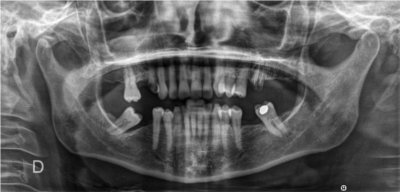

Images de panoramiques dentaire: